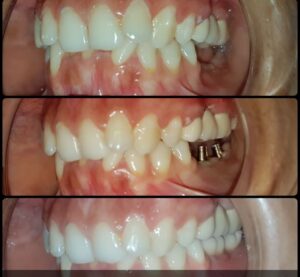

અમારી હોસ્પિટલ માં કરેલ ડેન્ટલ ઇમ્પ્લાન્ટ ના ફોટો